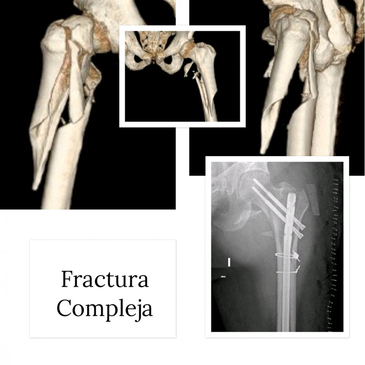

Dr. Rodrigo Aguirre Rojas is the best Orthopedic Surgeon in San Jose del Cabo, Mexico. Book your consultation for Hip and Knee Replacements in Los Cabos, Mexico at PlacidWay. Emergencies like Fractures and Dislocations are also evaluated and treated